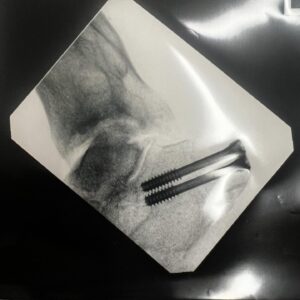

10.7K Likes – Blake Williams Instagram

Caption : 4 weeks down since some serious camber adjustment on the heel and a slight wheel alignment. All going well at this point, except the nightmares of Baltimore Dew tour 07 and eating shit doing someone that’s wasn’t necessary 🤦🏻♂️😂 hit up my #onlyFeet account for more VIP pics and private content 😂😂😂Likes : 10654

10.7K Likes – Blake Williams Instagram

Caption : 4 weeks down since some serious camber adjustment on the heel and a slight wheel alignment. All going well at this point, except the nightmares of Baltimore Dew tour 07 and eating shit doing someone that’s wasn’t necessary 🤦🏻♂️😂 hit up my #onlyFeet account for more VIP pics and private content 😂😂😂Likes : 10654

10.7K Likes – Blake Williams Instagram

Caption : 4 weeks down since some serious camber adjustment on the heel and a slight wheel alignment. All going well at this point, except the nightmares of Baltimore Dew tour 07 and eating shit doing someone that’s wasn’t necessary 🤦🏻♂️😂 hit up my #onlyFeet account for more VIP pics and private content 😂😂😂Likes : 10654

10.7K Likes – Blake Williams Instagram

Caption : 4 weeks down since some serious camber adjustment on the heel and a slight wheel alignment. All going well at this point, except the nightmares of Baltimore Dew tour 07 and eating shit doing someone that’s wasn’t necessary 🤦🏻♂️😂 hit up my #onlyFeet account for more VIP pics and private content 😂😂😂Likes : 10654

10.7K Likes – Blake Williams Instagram

Caption : 4 weeks down since some serious camber adjustment on the heel and a slight wheel alignment. All going well at this point, except the nightmares of Baltimore Dew tour 07 and eating shit doing someone that’s wasn’t necessary 🤦🏻♂️😂 hit up my #onlyFeet account for more VIP pics and private content 😂😂😂Likes : 10654

10.7K Likes – Blake Williams Instagram

Caption : 4 weeks down since some serious camber adjustment on the heel and a slight wheel alignment. All going well at this point, except the nightmares of Baltimore Dew tour 07 and eating shit doing someone that’s wasn’t necessary 🤦🏻♂️😂 hit up my #onlyFeet account for more VIP pics and private content 😂😂😂Likes : 10654

10.7K Likes – Blake Williams Instagram

Caption : 4 weeks down since some serious camber adjustment on the heel and a slight wheel alignment. All going well at this point, except the nightmares of Baltimore Dew tour 07 and eating shit doing someone that’s wasn’t necessary 🤦🏻♂️😂 hit up my #onlyFeet account for more VIP pics and private content 😂😂😂Likes : 10654

10.7K Likes – Blake Williams Instagram

Caption : 4 weeks down since some serious camber adjustment on the heel and a slight wheel alignment. All going well at this point, except the nightmares of Baltimore Dew tour 07 and eating shit doing someone that’s wasn’t necessary 🤦🏻♂️😂 hit up my #onlyFeet account for more VIP pics and private content 😂😂😂Likes : 10654